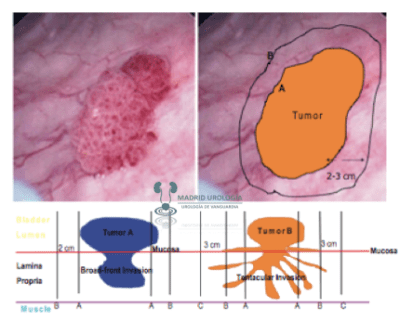

La extensión de la lesión debería alcanzar un margen de al menos 2 cm, debido a que evidencia anatomopatológica, demuestra que el crecimiento tumoral puede alcanzar esta distancia de penetración lateral. ***

En principio toda resección debe realizarse en profundidad hasta por lo menos alcanzar la grasa que se ve entre las fibras musculares y el tejido perivesical. ***

| Esquema gráfico que representa la extensión lateral y en profundidad del cáncer de vejiga. |